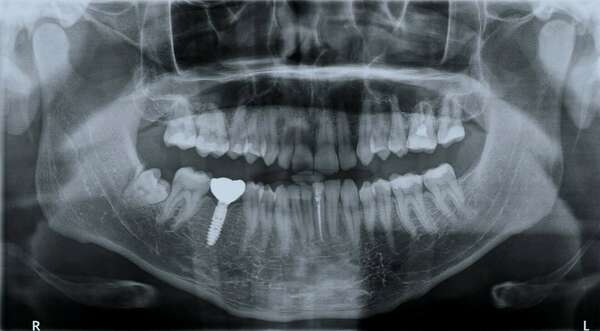

La méthode MIMI®-Flapless (Méthode d’Implantation Minimalement Invasive) désigne une technique de chirurgie implantaire sans ouverture de la gencive.

La technique Flapless

améliore la capacité

de la muqueuse à

cicatriser rapidement et

qualitativement, le tissu

cicatriciel vulnérable

ayant une surface

d’exposition plus faible.